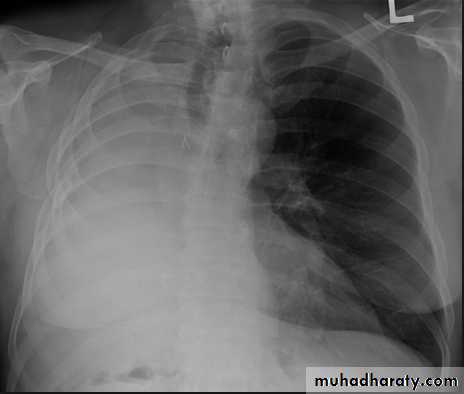

Massive pleural effusion with mediastinal shift to the left.

(A) Chest radiograph

(B) CT coronal reconstruction. A massive effusion displaces the mediastinum to the left. CT shows the important pleural effusion together with the enhanced atelectatic left lung.

Note also the depression of the right hemidiaphragm (arrows).